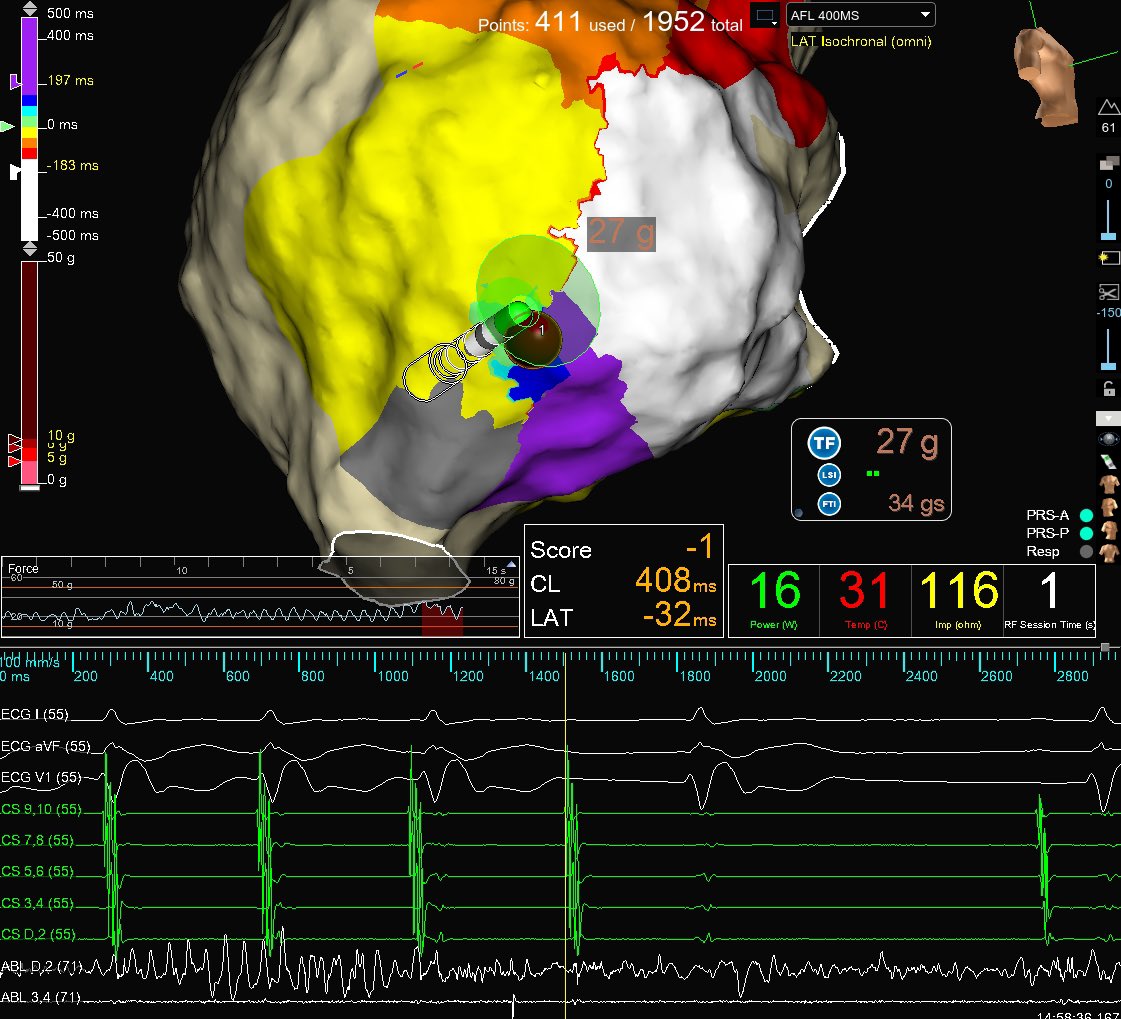

Very elusive LA Atypical AFL utilizing the reconnected LSPV. Circuit mapped on #EnsiteX with #HDGrid & #OT to identify the critical isthmus. Termination of tachycardia achieved within 1 second with a single RFA application. Map Credit: Brian Otto #mapmoreburnless

Very elusive LA Atypical AFL utilizing the reconnected LSPV. Circuit mapped on #EnsiteX with #HDGrid &amp; #OT to identify the critical isthmus. Termination of tachycardia achieved within 1 second with a single RFA application. Map Credit: <a href="/BrianOttoEP/">Brian Otto</a> #mapmoreburnless